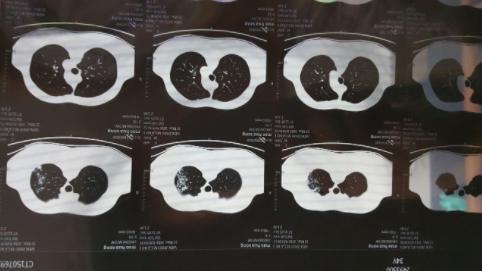

經(jīng)過了疫情的一波沖擊,大部分人都經(jīng)歷了一次新冠病毒的感染,陽康之后很多人都選擇拍胸部CT查看自己的身體情況,當(dāng)人們在看到自己的檢查單上寫著”肺部纖維灶“后嚇了一跳,大部分人詢問的問題都是”自己的肺部是不是纖維化了“、“肺部有玻璃陰影要緊嗎”?

對于人們最關(guān)注的這些問題,上海市胸科醫(yī)院呼吸與重癥醫(yī)學(xué)科副主任李峰表示,不必過度緊張,大部分人都只是出現(xiàn)了感染后的肺間質(zhì)異常,本身是沒有特別的其他癥狀,就像是一個傷痕,之后會慢慢恢復(fù)的,無需過多擔(dān)心,李峰表示,當(dāng)人在眼眶后檢查胸部CT,的確會發(fā)現(xiàn)肺部會有一些磨玻璃影,磨玻璃小結(jié)節(jié)等情況,這都是由于感染病毒之后才出現(xiàn)的,一般情況下不會再擴大,而且過一段時間就會慢慢康復(fù)。

對于之前感染新冠病毒之后出現(xiàn)了肺部感染的人群建議等康復(fù)之后觀察隨訪,等到三個月到6個月左右,復(fù)查CT,如果沒有其他不適的癥狀,可以等到陽康之后3~6個月左右再檢查胸部CT,李峰解釋道,對于輕癥的肺炎患者,做檢查顯示肺部有纖維條縮影的情況無需特殊的干預(yù)。

專家表示,正常情況下,肺部出現(xiàn)纖維灶并不代表一定是壞的,這就像是人身體某個部位被劃傷之后留下的一個傷疤,不用特殊治療,也不用吃藥,肺纖維化分為兩種,一種是指特發(fā)性肺纖維化,第2種是繼發(fā)性纖維化,人們感染新冠后出現(xiàn)的屬于繼發(fā)性肺纖維化,重重就輕的,甚至充不上肺纖維化,所以無需過度擔(dān)心。